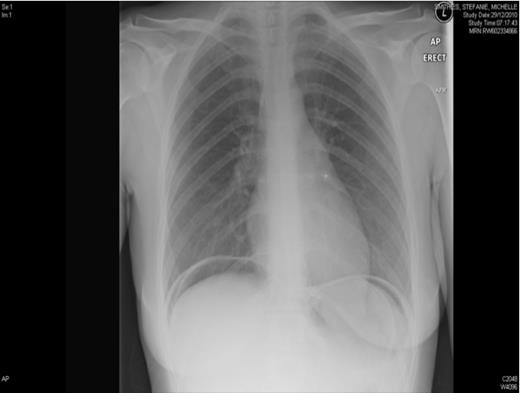

She was seen by Surgeons who advised for an erect chest x-ray which showed gas under the diaphragm implying the diagnosis of perforated peptic ulcer disease. Her past medical history was unremarkable. She had undergone abdominal hysterectomy three months before for menorragia. Her post operative review was uneventful and vault has healed well.

In view of the clinical symptoms and radiological findings patient was taken for emergency laparatomy. There was no perforation of viscus but there was a defect noted in the vaginal vault. The Gynaecology team was called in and the vault was sutured with interrupted sutures.

In our patient the acute symptoms and X-Ray findings lead for an early laparatomy. This condition could have been managed conservatively if the pain has not been severe. The vault repair can be corrected laparoscopic or vaginally and a major laparatomy could be avoided